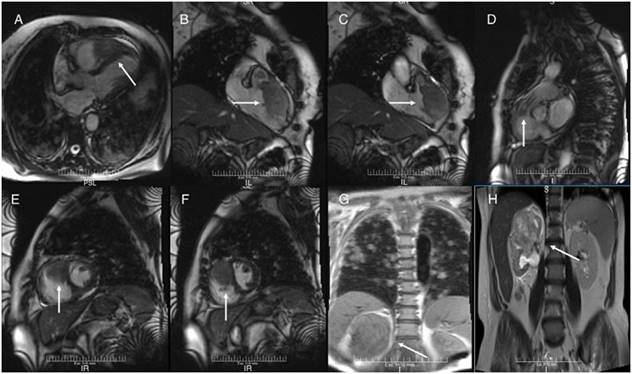

93 lpm, frecuencia respiratoria de 26 rpm, presión arte- rial 110/80 mmHg. A la auscultación cardiaca presentaba soplo eyectivo en foco pulmonar grado III/VI, irradiado a foco aórtico accesorio, eyectivo, grado III/IV. En la auscultación pulmonar se encontraron crepitantes finos y gruesos basales bilaterales. En ECG se observó elevación del punto J y ondas T negativas, simétricas de V1 a V4 y discreta elevación de ST en cara inferior (fig. 1). Tiene como ante- cedente imagen quística gigante en riñón derecho, a la cual realizaron en diversas oportunidades drenaje percutáneo, pero no realizaron biopsia ni indicaron otro tratamiento. También refirió infecciones respiratorias a repetición, con último episodio dos semanas antes de la hospitalización. En la radiografía de tórax se observaron imágenes redondeadas de aspecto algodonoso con distribución difusa en ambos campos pulmonares. Se solicitaron enzimas cardiacas y se encontraron dentro de límites normales en tomas seriadas; dímero D resultó negativo. Se realizó ecocardiograma transtorácico donde se observó el ventrículo izquierdo (VI) no dilatado con patrón geométrico normal y fracción de eyección preservada, sin trastornos de cinesia regional; el ventrículo derecho (VD) no dilatado con función sistólica preservada, con imagen ecorrefringente adherida al ápex del VD, de 36x20 mm aproximadamente, que se extendía hasta el tracto de salida del VD; presión sistólica de la arteria pulmonar normal. Ante tales hallazgos, se solicitó resonancia magnética de tórax y abdomen, con contraste (fig. 2), que reportó lesión ocupante de espacio (LOE) heterogénea en cavidad del VD, de gran tamaño 41x79x24 mm, que infiltraba las paredes y ocasionaba disrupción del pericardio visceral, con bordes irregulares; generando obstrucción dinámica del tracto de salida del VD. Realce tardío heterogéneo con áreas de baja señal de intensidad en relación con necrosis tumoral y hemorragia. Se planteó sarcoma indiferenciado o lesión metastásica. Riñón derecho con pérdida de la morfología, lesión sólida heterogénea de bordes mal definidos, 6.9x5.8 cm. En ambos pulmones, imágenes nodulares múltiples, con diámetros entre 0.5 y 2 cm, de distribución aleatoria, algunas con contacto pleural y con realce significativo de todas las lesiones.

Se descartó cardiopatía isquémica ante enzimas cardiacas negativas y ausencia de trastornos de cinesia en ecocardiograma, y se planteó que los cambios electrocardiográficos eran debidos a infiltración tumoral en el VD, y que esta era de origen metastásico, secundarias a LOE renal. La paciente egresó con valoración ambulatoria planificada por servicio de oncología. Dos meses después del alta, ingresó en el área de urgencias por presentar trombo- sis venosa profunda en ambos miembros inferiores, presentó deterioro progresivo del estado general, y falleció durante la hospitalización.

Figura 2: Resonancia magnética. A) Vista anatómica de 2 cámaras, en la que se ve tumor desde el ápex del VD hasta la parte media del VD, adherido también a la pared libre del VD y al septum interventricular (flecha). B y C) Vista lateral del VD en diástole y sístole respectivamente. En esta se confirma la extensión del tumor al tracto de salida del VD, así como también la obstrucción dinámica durante la sístole (flecha). D) Vista lateral del tracto de salida del VD. Se observa tumor extendido al origen de la arteria pulmonar (flecha). E y F) Vista de eje corto, donde se puede apreciar el tumor intracavitario y su extensión a través de la pared del VD hasta el pericardio (flecha). G y H) Resonancia magnética de tórax y abdomen. Se observa LOE de gran tamaño en riñón derecho e imágenes metastásicas en ambos pulmones (flecha).

ducir consecuencias severas como embolismos sistémicos o pulmonares, obstrucción del flujo de entrada o del tracto de salida del ventrículo afectado. En esta paciente se observó infiltración en ápex del VD y del tracto de salida del VD con obstrucción dinámica del mismo, y disrupción del pericardio visceral.

Los tumores pueden alcanzar el corazón mediante 4 vías: diseminación hematógena, diseminación linfática, extensión transvenosa y extensión directa. Ciertos tumores como el carcinoma de células renales y el carcinoma hepatocelular pueden extenderse dentro de la vena cava inferior y crecer dentro de la aurícula derecha (extensión transvenosa)5. En nuestra paciente, debido a sus antecedentes, se planteó que el tumor primario era del sistema renal, el cual hizo metástasis en pulmones y en VD. El estado hipercoagulable relacionado con el cáncer también puede causar la formación de trombos in situ1.

La principal herramienta de detección es el ecocardiograma transtorácico, para establecer diagnóstico, localización y extensión de masas cardiacas. En algunos casos se debe usar el ecocardiograma transesofágico para mejor evaluación del patrón morfológico. La resonancia magnética cardiaca es excelente herramienta para diagnosticar, ubicar y medir LOE6. En este caso se realizó RM de tórax y abdomen para determinar la morfología del LOE renal y presencia de otras lesiones metástasis en ambos pulmones.